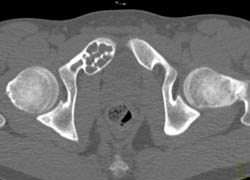

Sclerotic Bone Metastases